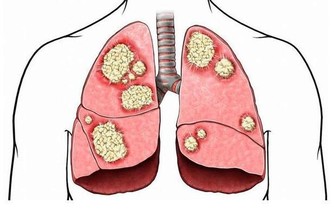

直腸癌有哪些先兆的特徵?

直腸癌先兆和黏液便、黑便、大便不成形、排便習慣變化、以及經常性的腹瀉腹脹有關。出現以上情況不要以為只是腸胃出了問題,其實有些也是罹患直腸癌的前兆。

①長期便秘是大腸癌的誘因,你是否有如廁卻苦苦掙扎得不到解脫的經歷?長期便秘可導致宿便,滯留在便中的致癌物濃度越來越高,而如果腸壁長期與這些致癌物質接觸,就易結、直腸癌發生病變。

便秘不僅是直腸癌的誘因,同時也是結直腸癌的表現,由於靠左側的降結腸較為狹窄,如果有腫瘤生成,往往會發生腸道的梗阻,導致嚴重便秘。

②排便習慣的變化如平常排便較為乾燥,卻突然變稀,或是由稀變乾;

排便習慣的變化還表現在排便次數出現異樣,有些是一天一次則變成二、三次,或是反之。

如果有腹部不適症狀、疼痛、局部有腫塊,大便性狀改變明顯,(由幹變稀,有鮮血、黏液;大便不成固定形狀,變扁變細)。

即排便和平常的規律不一樣,發生變化,應及早到醫院進行排查。

③出現便血要排查直腸癌需警惕痔瘡和直腸癌可能有存在一些類似的症狀,如便血。

但結直腸癌的便血和痔瘡的略有不同。

首先痔瘡可發生在任何人身上,而直腸癌的患者多為中老年人。

痔瘡患者的大便有血,是因排便時擦傷患處,不與糞便相混合更沒有黏液存在。

而直腸癌患者的大便則常混有血液、黏液和膿液等。

患者也可有不同程度的肛門下墜感、便意無盡感,有時可出現腹瀉。

直腸癌的先兆特徵需要引起注意,從細節著手,遠離直腸癌。